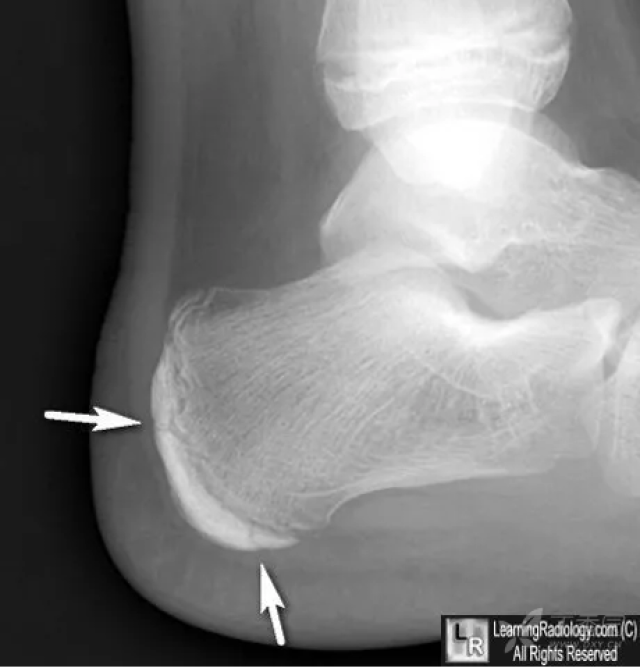

跟骨x线显示跟骨刺综合征

跟骨正常与变异影像学表现